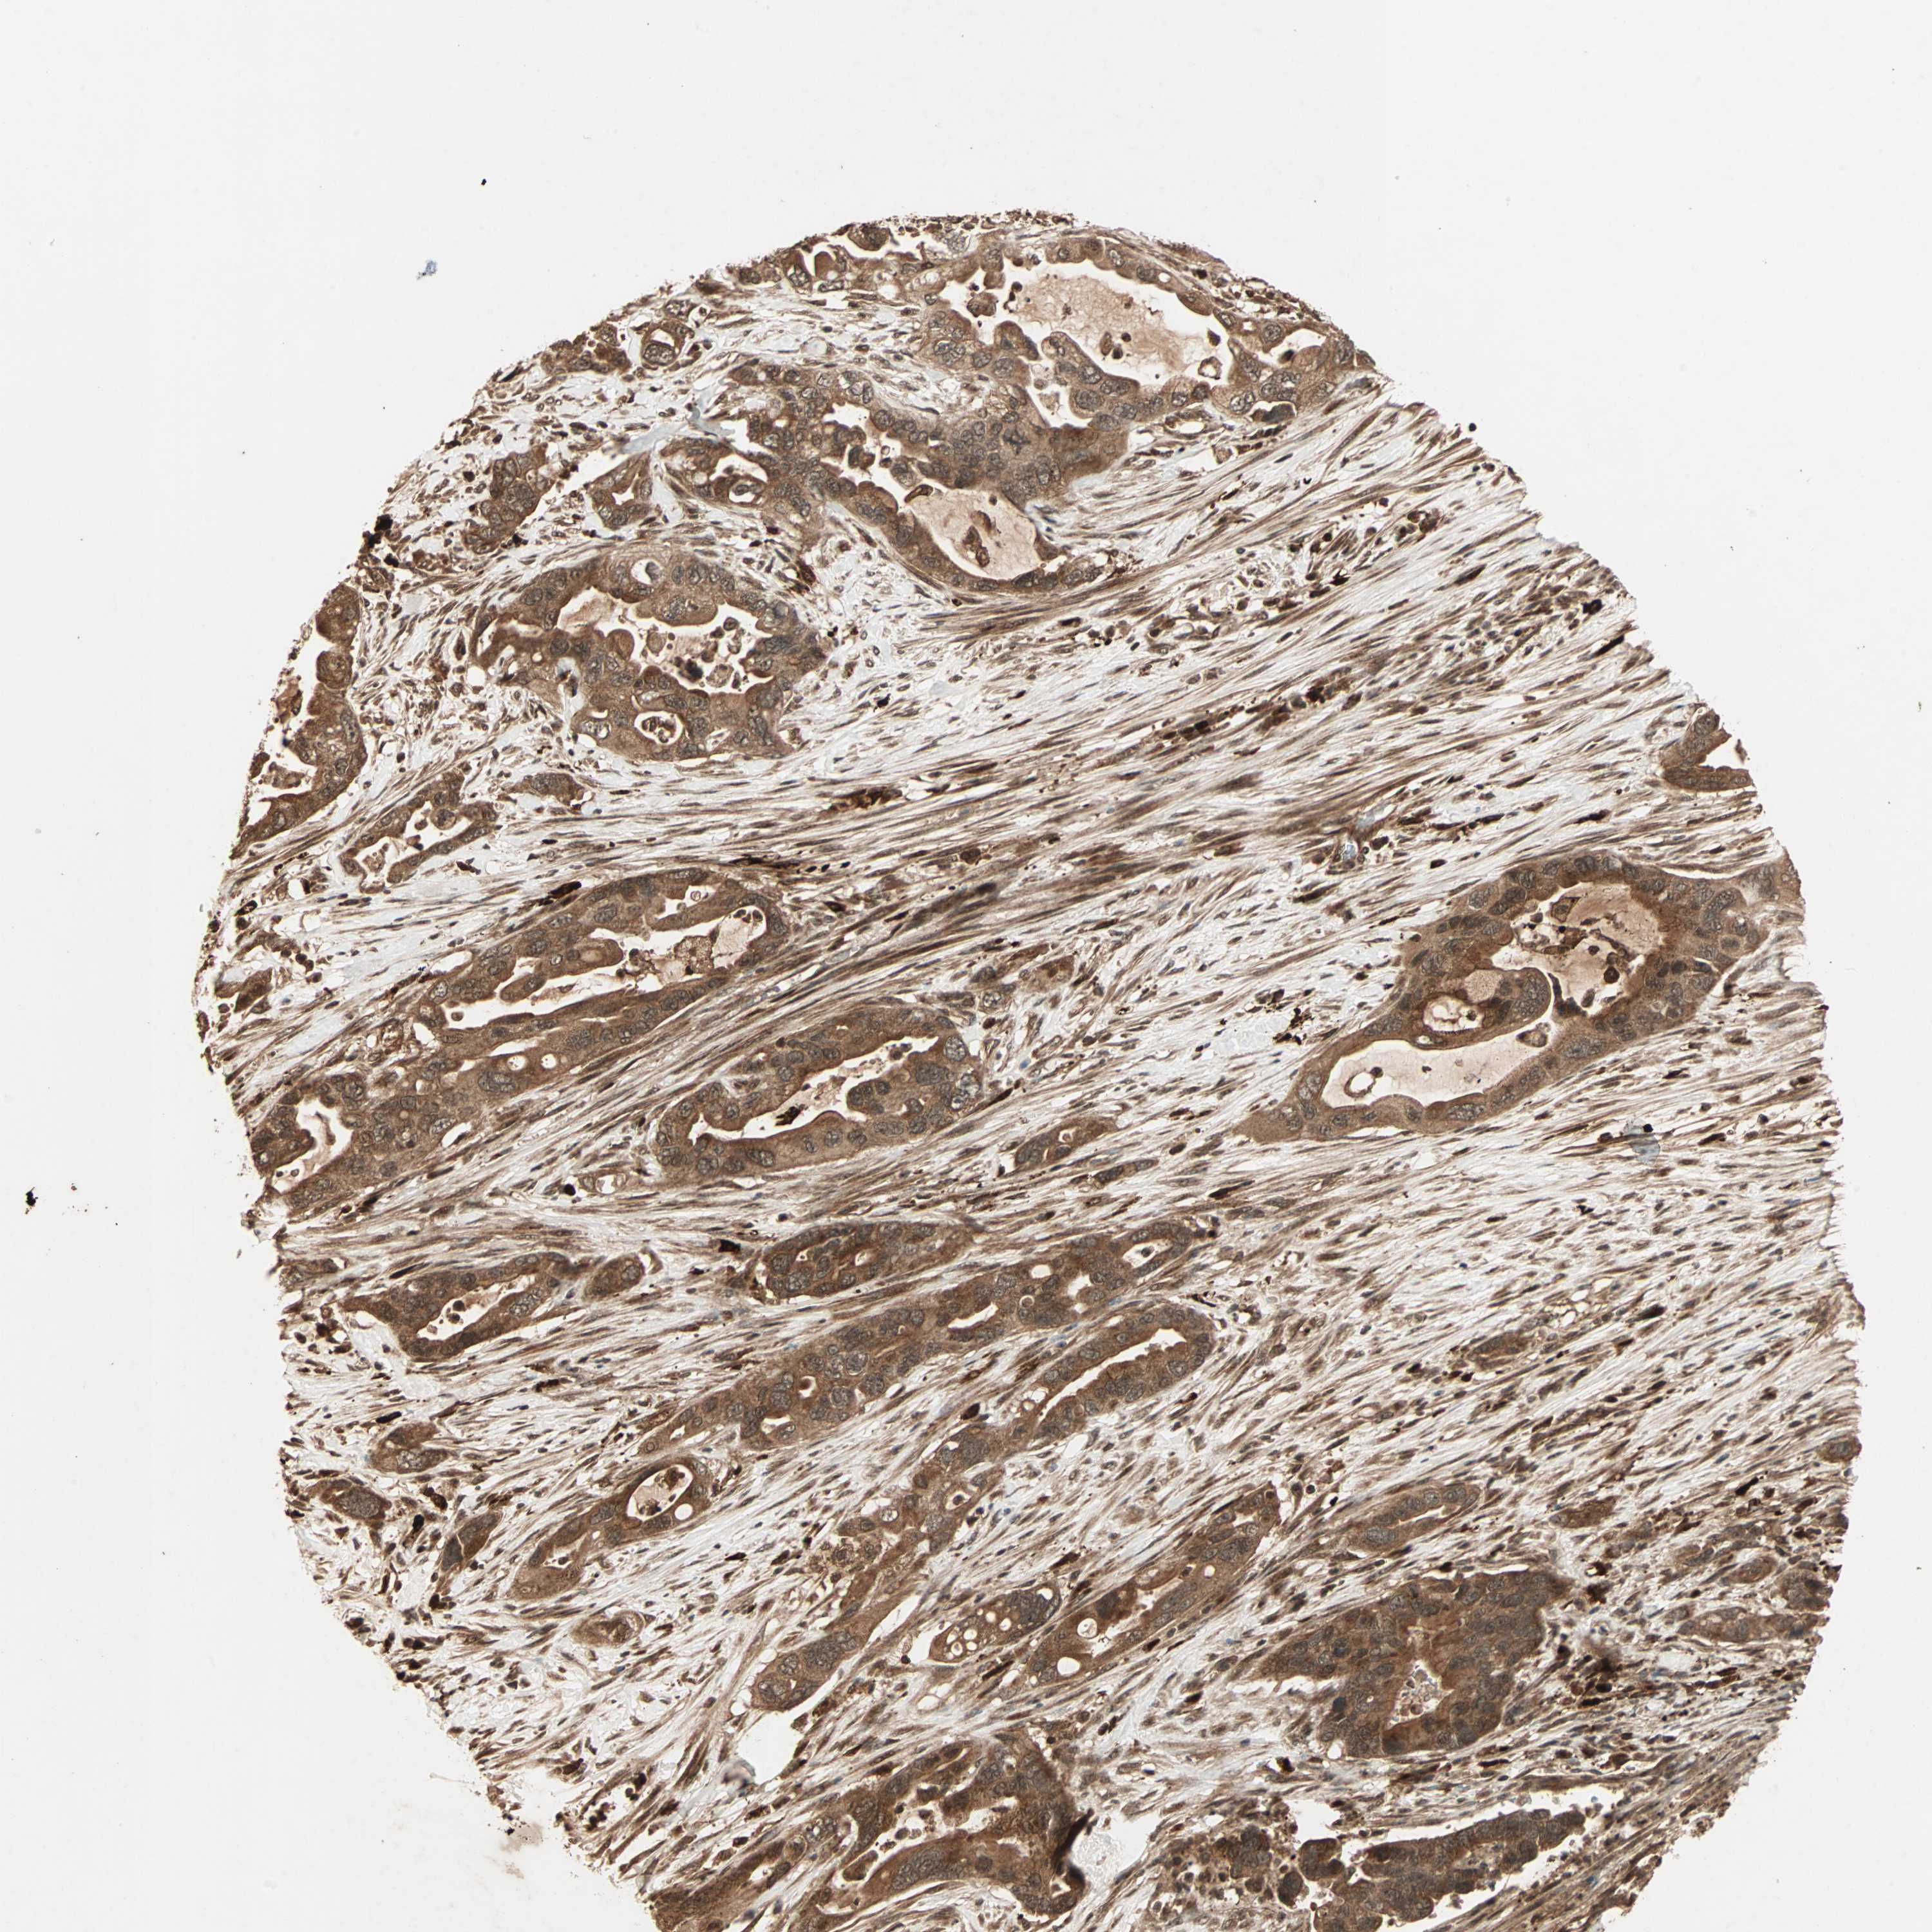

PANCREATIC CANCER - Protein expressioni

A mouse-over function shows sample information and annotation data. Click on an image to view it in a full screen mode. Samples can be filtered based on level of antibody staining by selecting one or several of the following categories: high, medium, low and not detected. The assay and annotation is described here.

Note that samples used for immunohistochemistry by the Human Protein Atlas do not correspond to samples in the TCGA dataset.

Antibody stainingi

Antibody staining in the annotated cell types in the current human tissue is reported as not detected, low, medium, or high, based on conventional immunohistochemistry profiling in selected tissues. This score is based on the combination of the staining intensity and fraction of stained cells.

Each image is clickable and will lead to virtual microscopy that enables deeper exploration of all samples and also displays staining intensity scores, fraction scores and subcellular localization as well as patient and tissue information for each sample.

Antibody HPA017910

Antibody HPA019492

Antibody CAB008096

Staining

High

Medium

Low

Not detected

Intensity

Strong

Moderate

Weak

Negative

Quantity

>75%

75%-25%

<25%

None

Location

Nuclear

Cytoplasmic/membranous

Cytoplasmic/membranous,nuclear

Adenocarcinoma, NOS

Adenocarcinoma, metastatic, NOS